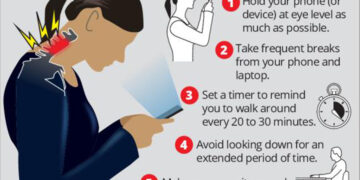

Read moreমেহেরুন নেসা দিনে পাঁচ ঘণ্টা বা তার বেশি সময় মোবাইল ফোন, ল্যাপটপ চালানোর ফলে প্রতি ১০ জনের ৭ জনই টেক্সট...